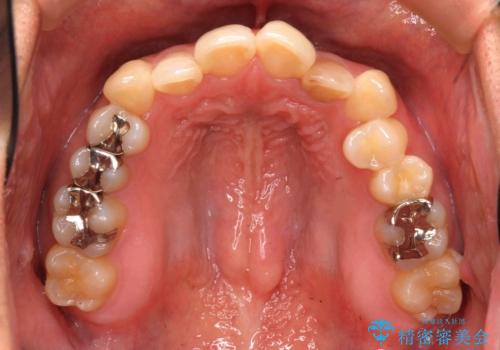

埋まっている奥歯を引っ張り出す インビザライン矯正

- 前歯のがたつきと左下の歯がうまっているとのことで、矯正治療を希望されました。

埋まっている奥歯を並べることで、その後ろの倒れ込んだ歯を整直させることができました。

引っ張り出すことはマウスピース矯正では難しい為、埋まっている歯を並べるスペース確保と、引っ張り出すのに、ワイヤーを用いた部分矯正を行なっています。

上の歯はマウスピース矯正で、奥歯を後ろに下げて、左のかみ合わせのズレを直しています。

上下とも非抜歯で並べています。